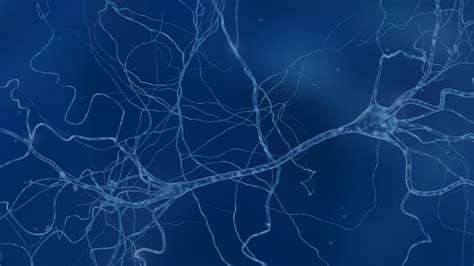

Abstract representation of brain health